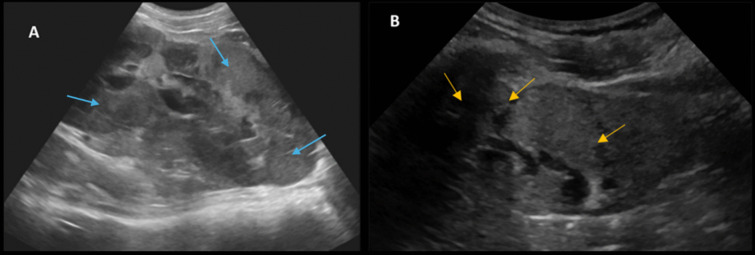

Methods: We present a rare case of primary bilateral renal diffuse large B-cell lymphoma in a teenage girl presenting with kidney failure (eGFR of 7 ml/min/1.73 m2), proposing a practical approach to optimize chemotherapy on kidney replacement therapy. We discuss diagnostic methods, the management and adjustment of chemotherapy and hyperhydration protocols, and the tailoring of highly efficient hemodiafiltration sessions to grant sufficient drug exposure while avoiding drug accumulation and toxicity in the context of kidney failure.

Results: This approach permitted a substantial reduction of chemotherapy adverse effects while inducing remission and partial recovery of kidney function in our patient, with hemodialysis discontinuation after 6 months, and an eGFR that had improved to 28 ml/min/1.73 m2 at 12 months.